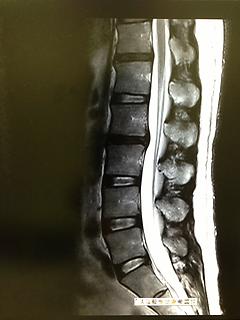

MRIの結果、椎間板ヘルニアということです。

写真とっていきなさい、って勧めてくれたので遠慮なくパシャリ。

背骨初公開です(笑)

真中らへんの、椎間板が黒くなって背骨からはみだしてるのが素人目でもわかりますね。